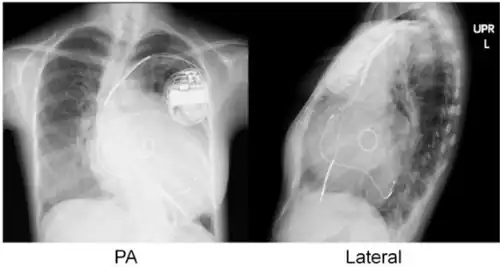

| Implanted cardiac resynchronization device | |

Cardiac resynchronisation therapy (CRT or CRT-P) is the insertion of electrodes in the left and right ventricles of the heart, as well as on occasion the right atrium, to treat heart failure by coordinating the function of the left and right ventricles via a pacemaker, a small device inserted into the anterior chest wall.[1]

CRT requires the placement of an electrical device for biventricular pacing, along with placement of (at least) two pacing leads, to facilitate stable left ventricular and right ventricular pacing. For all elements, the first stage of the process is local anaesthetic followed by incision to allow for approach from the appropriate vein. From here, the leads and device can be inserted.[1]

Device placement

The device is inserted in a subcutaneous pocket created by the surgeon, the choice of left or right side of the chest wall is determined mainly by the patient's preference or location of preexisting device. The device, similar to that of a traditional pacemaker, is generally no larger than a pocket watch and has inserts for the electrode leads.[1]